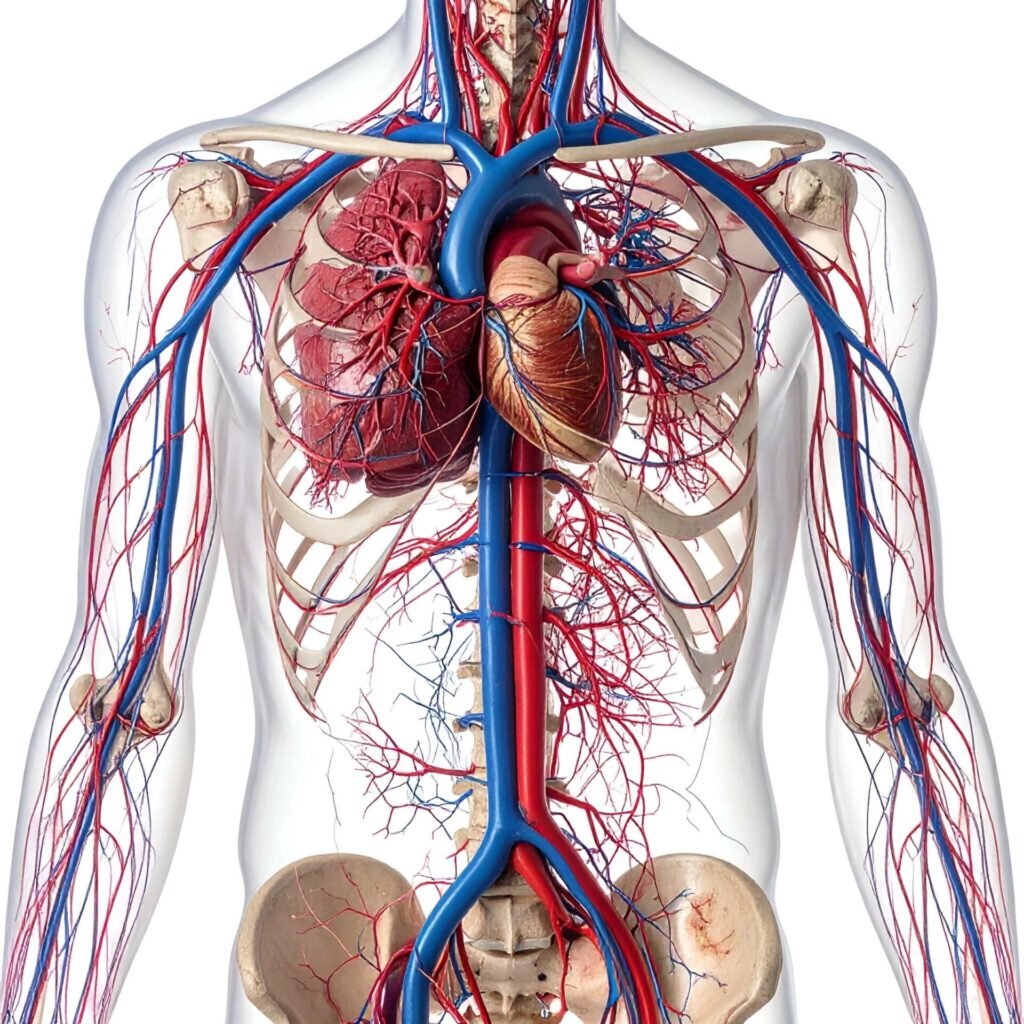

CARDIOVASCULAR

Cardiovascular Disease— Major global burden

✅ Strong evidence — Chronic inflammation (metaflammation) is a core driver of:

• Atherosclerosis / cardiovascular disease

(Approx. ~7–8% diagnosed global prevalence; much higher subclinical burden)

Heart disease is a chronic inflammatory condition, strongly influenced by lifestyle factors.